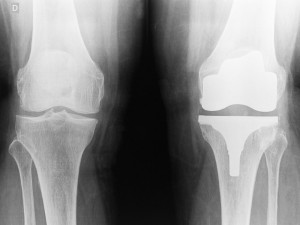

Des traitements de surface innovants pour les implants et les instruments

Société suisse du Groupe Horatec, Steiger Galvanotechnique SA se positionne comme un leader dans le traitement de surface métallique, avec des procédés innovants et des prestations adaptées aux besoins de l'horlogerie mais aussi de l'industrie [...]